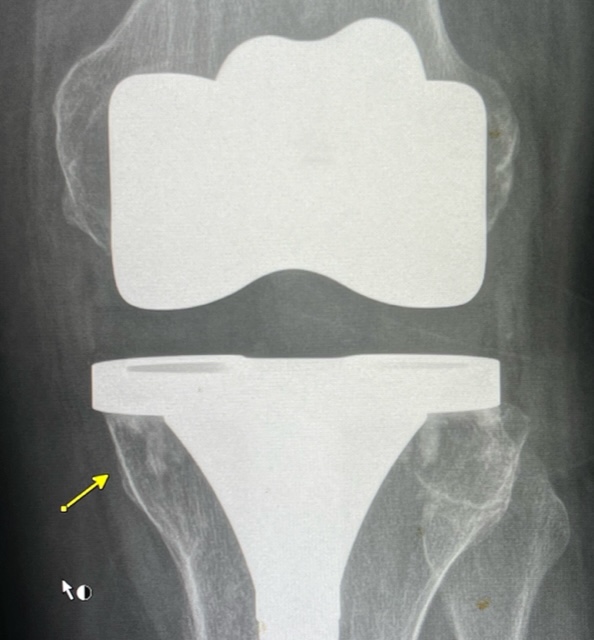

Dear OCAD colleagues I encountered this MRI today. This is a 67 year old lady with known left knee replacement and revision in April 23. She started to have intense, medial knee pain on weight-bearing, biting; pinching type. I see the signal abnormality, at the medial tibial Metastasis away from the prosthesis. It is strange